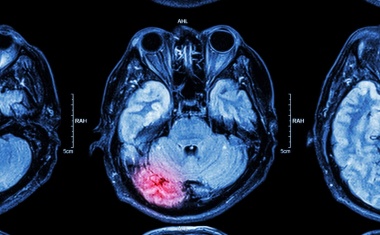

Eine durch Arteriosklerose bedingte Verengung einer Halsschlagader (Carotisstenose) kann das Schlaganfallrisiko erhöhen. Operation und Stent sind laut einer aktuellen Studie gleichwertig zur Schlaganfallprophylaxe geeignet.